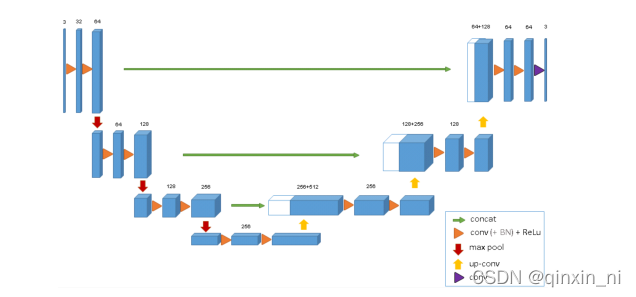

(1) 使用全卷积神经网络。(全卷积神经网络就是卷积取代了全连接层,全连接层必须固定图像大小而卷积不用,所以这个策略使得,你可以输入任意尺寸的图片,而且输出也是图片,所以这是一个端到端的网络。)

(2) 左边的网络是收缩路径:使用卷积和maxpooling.

(3) 右边的网络是扩张路径:使用上采样产生的特征图与左侧收缩路径对应层产生的特征图进行concatenate操作。

(4) 最后再经过两次反卷积操作,生成特征图,再用两个1X1的卷积做分类得到最后的两张heatmap,例如第一张表示的是第一类的得分,第二张表示第二类的得分heatmap,然后作为softmax函数的输入,算出概率比较大的softmax类,选择它作为输入给交叉熵进行反向传播训练。